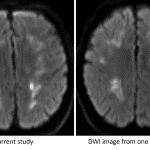

- Patchy and confluent areas of T2/FLAIR signal hyperintensity in the bilateral cerebral white matter, advanced for patient age

- Corresponding patchy restricted diffusion